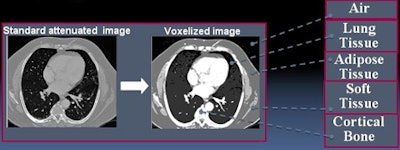

Each dataset was then "voxelized" to create a patient-specific virtual phantom. Each voxel was assigned a material type based on a priori global HU classification intervals per the International Commission on Radiation Units and Measurements Report 44.